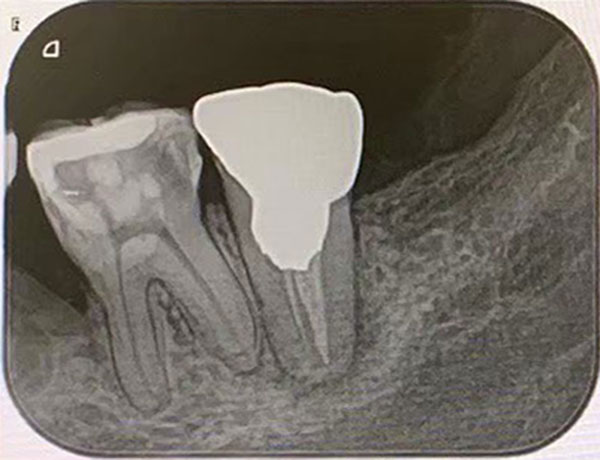

主訴: 噛むと痛い、奥歯が違和感ある

保険治療では発見することが難しい4つ目の神経を

歯を大きく削らずに見つけられます。